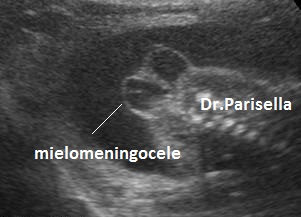

La spina bifida aperta è caratterizzata da un difetto osseo posteriore delle vertebre, interessamento a tutto spessore della cute e protrusione del contenuto spinale attraverso il difetto osseo. Il contenuto spinale può essere rappresentato da una tasca contenente le sole meningi (meningocele) o da una tasca contenente meningi e tessuto nervoso (mielomeningocele); più frequentemente il difetto spinale si localizza a livello del tratto lombo-sacrale della colonna vertebrale.

Nelle forme aperte la diagnosi ecografica prenatale si basa sui seguenti segni indiretti (1,2,3) e diretti(4,5):

5) mielomeningocele: formazione cistica settata sovrapposta alla schisi vertebrale.